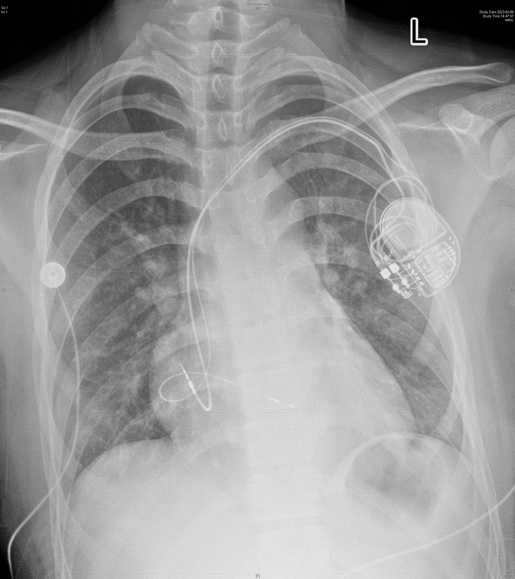

鲁网2月13日讯 2月7日,山东第一医科大学附属省立医院(山东省立医院)儿科主任、小儿心脏科主任韩波教授带领团队,成功为一名13岁患儿植入山东省首例左束支起搏模式的3.0T双腔抗核磁心脏永久起搏器。

患儿出生后即被发现心脏扩大伴完全性左束支传导阻滞,7年前进展为Ⅲ度房室传导阻滞,24小时平均心率为41次/分,左心室显著扩大,亟需植入心脏永久起搏器。2月6日下午,小儿心脏科全体医务人员进行术前讨论,并为患儿做好充分的术前准备。2月7日上午,韩波教授在介入诊疗中心为患儿成功实施手术,采用了更符合生理特点的左束支起搏方式。经测试,起搏器各项功能良好,患儿安全返回病房。